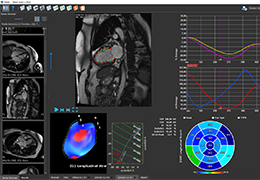

ANYTHINK 经导管主动脉瓣膜置换术分析系统